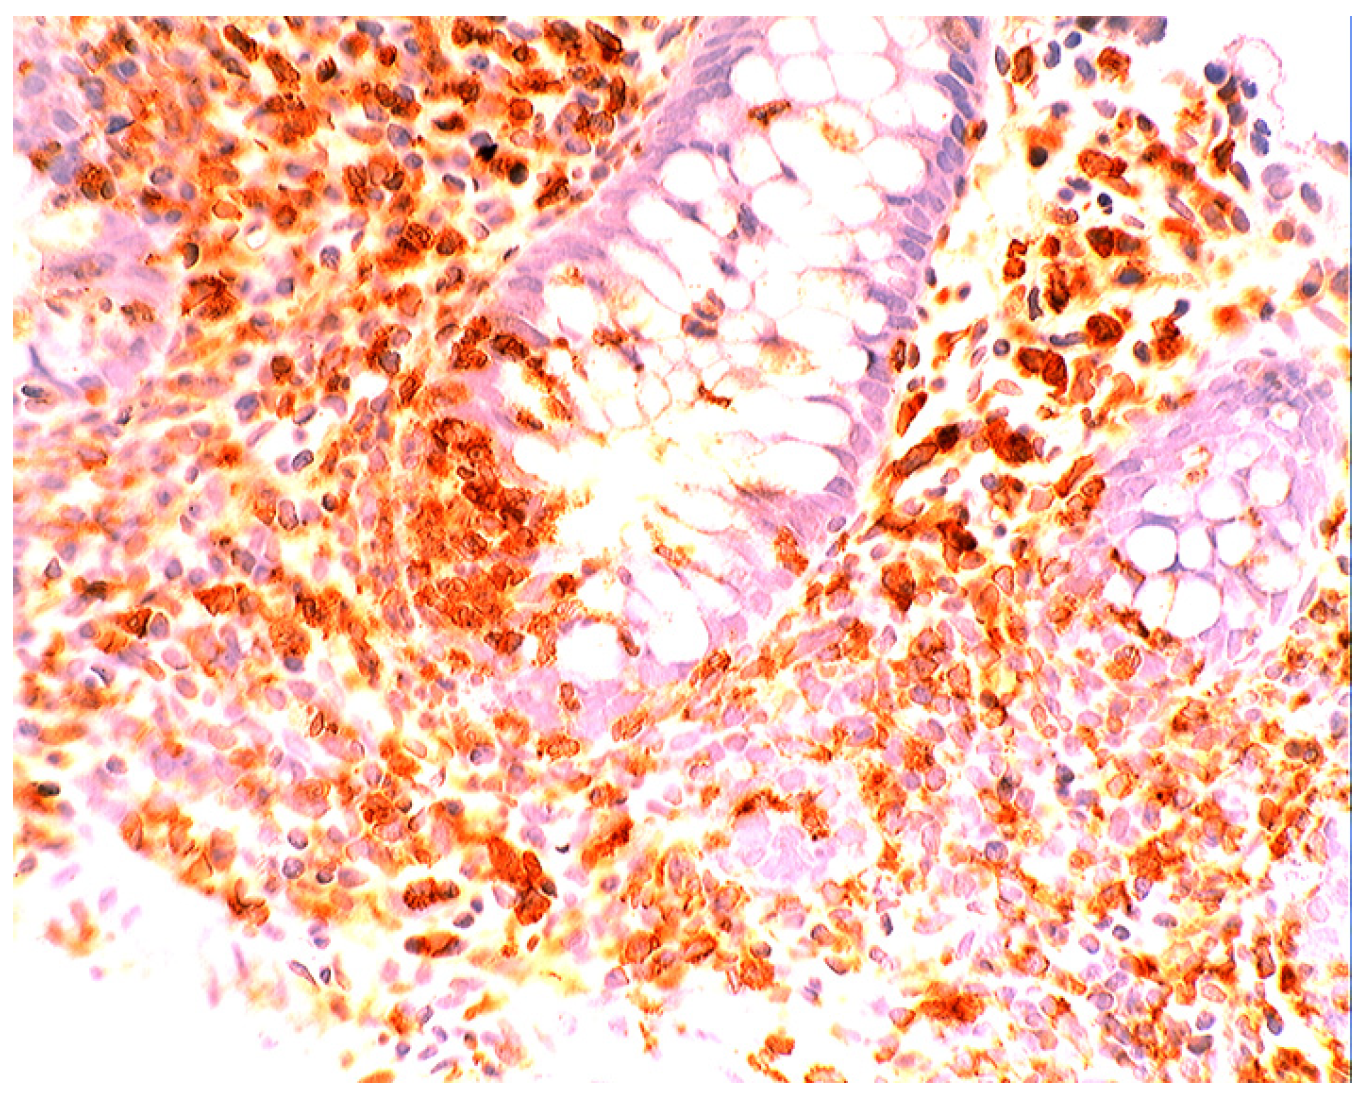

In active ulcerative colitis, lysozyme is up-regulated in metaplastic Paneth cells (left colon) and in the deep half of the crypts (Figure 14). In ulcerative colitis in remission, lysozyme is up-regulated in metaplastic Paneth cells [9] (left colon, Figure 15). No lysozyme expression is recorded in the crypts. In Crohn’s colitis lysozyme up-regulation is found in metaplastic Paneth cells (left colon), in the crypts as well as in the lamin propria mucosae [9] (Figure 16). The increased lysozyme production in the colonic mucosa in patients with inflammatory bowel disease may highlight an amplified mucosal protection against the pathogenic bacteria proliferating in the colonic microenvironment in these patients [70,71,72,73,74,75,76,77,78,79,80,81].

Figure 16.

Crohn colitis: Marked lysozyme immunoreactivity in macrophages in the lamina propria and in epithelial cells at the bottom of the crypts (lysozyme immunostain, ×20).